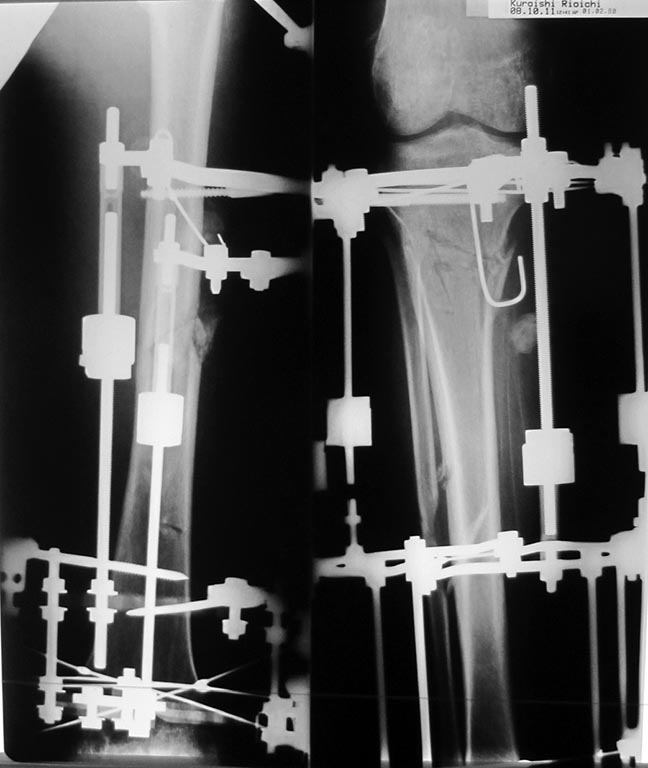

Друзья - коллеги, Пациент 27 лет приехал для удлинения роста по эстетическим показаниям. Метод: крослатеральное двухэтапное удлинение голеней 4см и бедер 3 см. Между этапами удлинения уезжал к себе домой в Японию на реабилитацию. Между этапами удлинения движения в коленных суставах разгибание полное сгибание 90-85. После выписки (февраль 2012) даны соответствующие указание постепенно возрастающей нагрузки и ЛФК коленных суставов.

Не совсем понял что означает "крослатеральное 2-х этапное удлинение". Видимо был аппарат и косопоперечная поднадкостничная остеотомия на голенях.- На снимках голеней видно. А бедра как удлинялись?- Уровень? Тоже аппаратом?

Возможно( ни в чем не уверен) но причина ,что пошли высоковато ,через бугристось на голенях и собственная связка так же вытягивалась, смещая надколенник вниз? На рентгене же связки оссифицированы,больше справа.

Высылаю снимки, свидетельствующие, что уровень остеотомий вроде как обычный, повторюсь, подобного осложнения после удлинения я не встречал ни у себя ни

в литературе. Сейчас на первое место встает вопрос как помочь данному пациенту. У кого есть опыт лечения patella baja?

Остеотомия высокая, почти на уровне бугристости, так что область прикрепления связки надколенника близко. Я бы делал на 2-3 см ниже. Удлинять на уровне диафиза стало особенно актуально в свете смены аппарата на гвоздь по окончании удлинения.